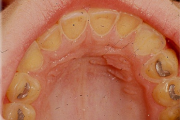

Hambakaaries